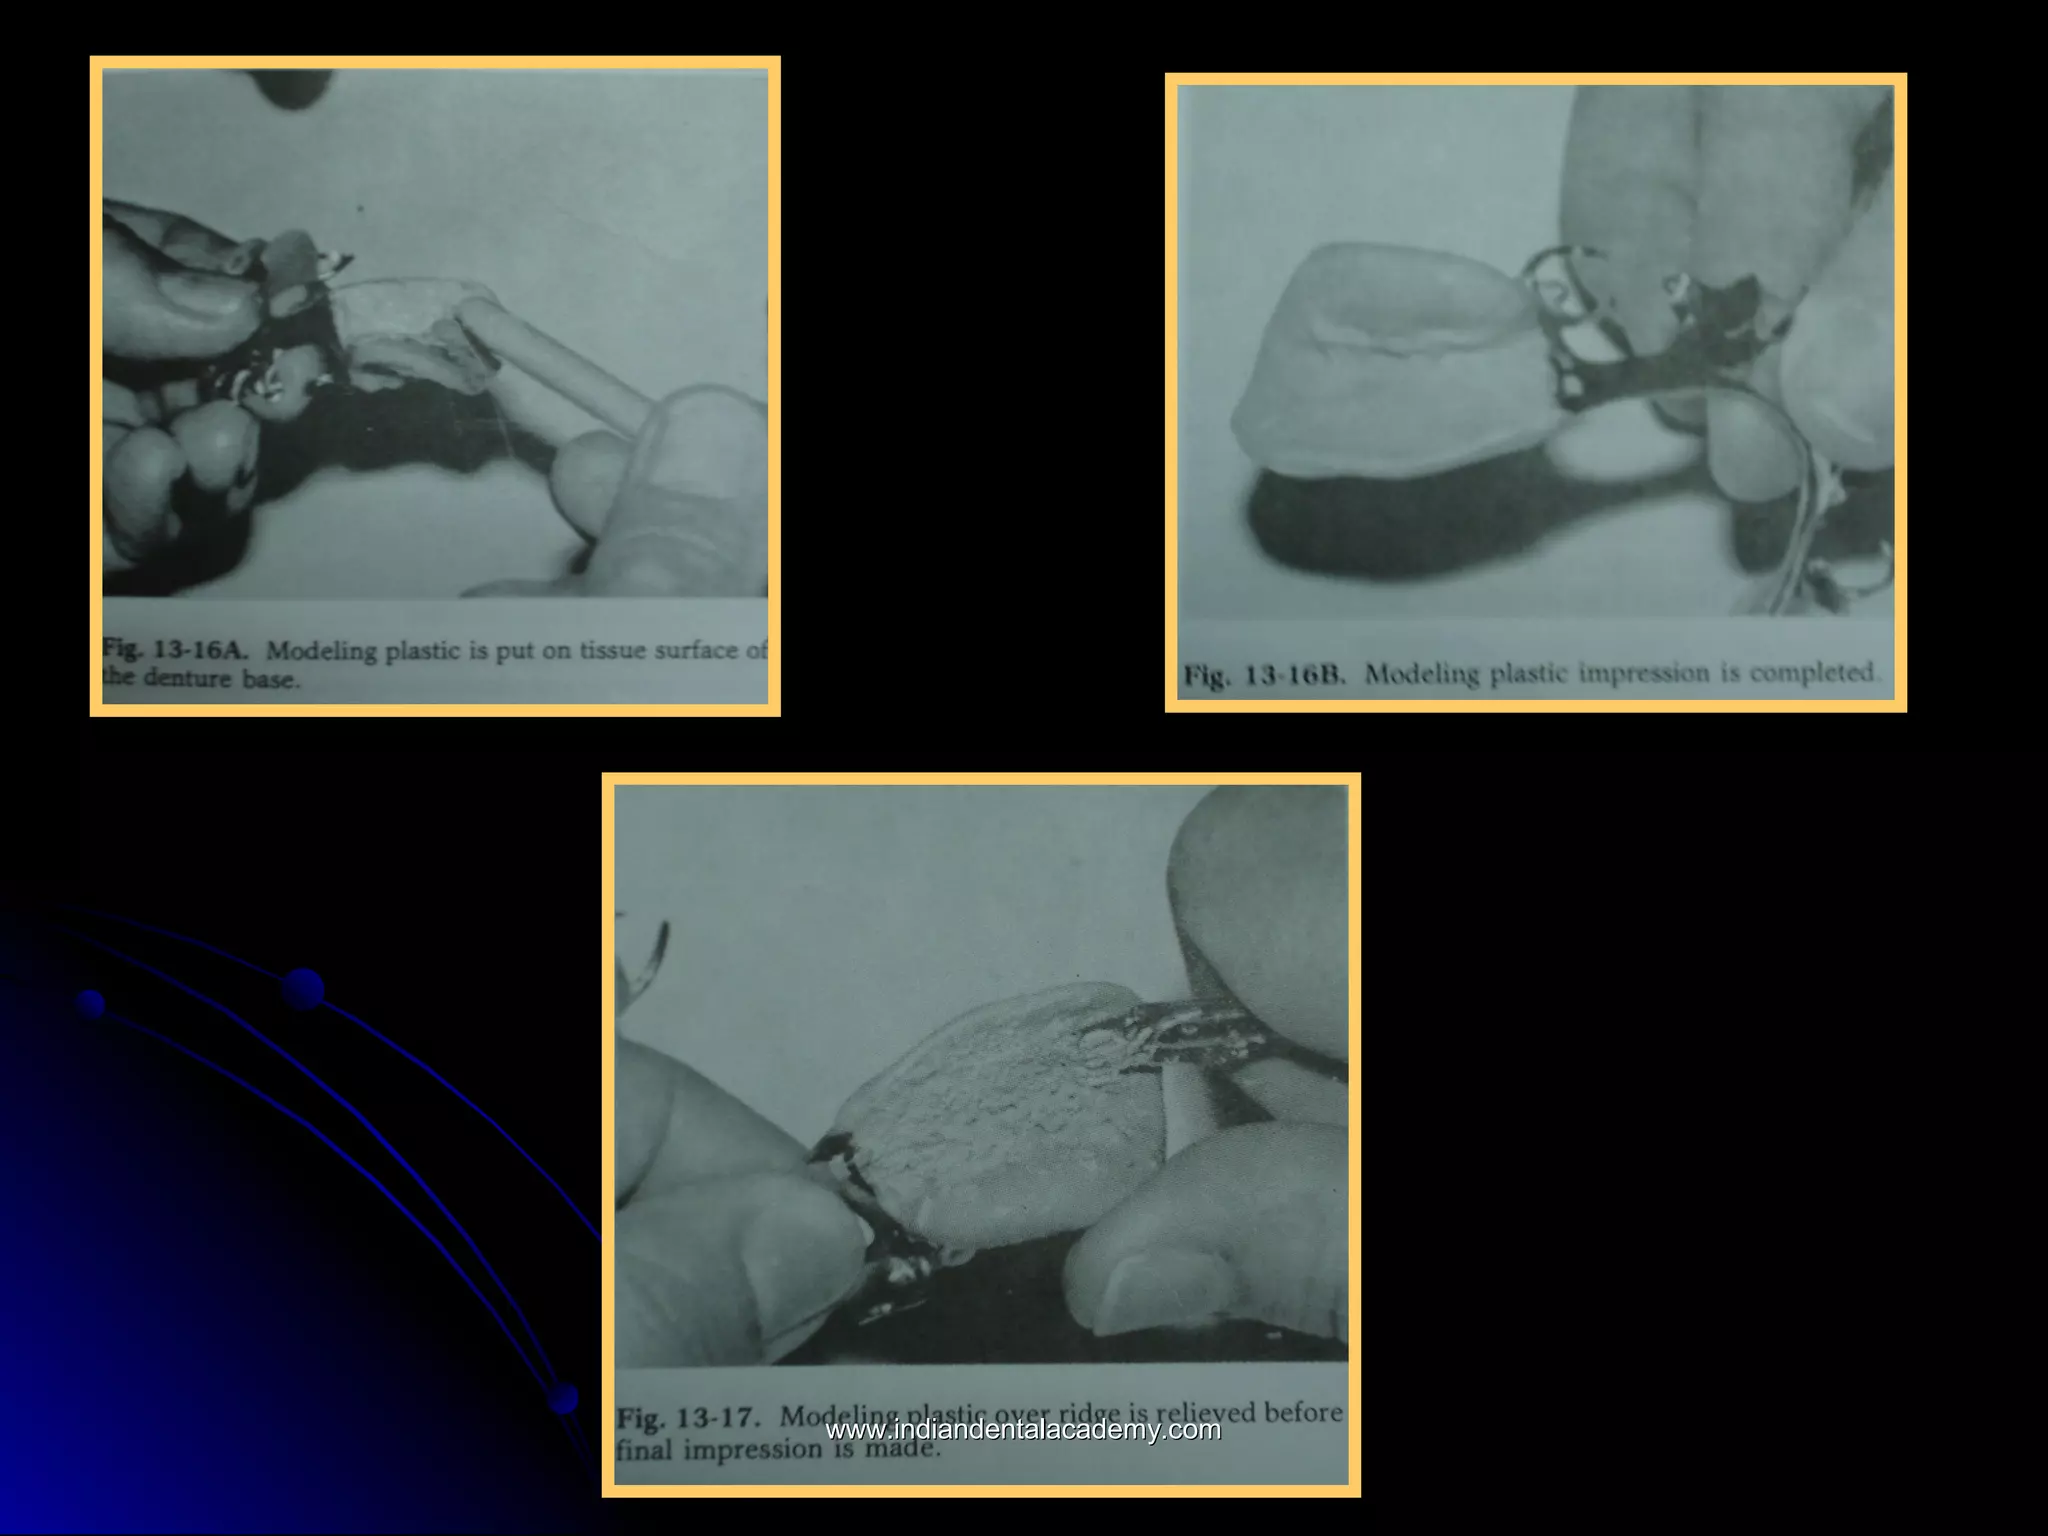

The portion of the technique that introduces theThe portion of the technique that introduces the

greatest hazard is the making of the relinegreatest hazard is the making of the reline

impression. The patient must maintain the mouth inimpression. The patient must maintain the mouth in

a partially open position while the border moldinga partially open position while the border molding

and impression are being accomplished because:and impression are being accomplished because:

1.The border tissues, cheek, and tongue are thus1.The border tissues, cheek, and tongue are thus

best controlled andbest controlled and

2.The relationship between the partial denture frame2.The relationship between the partial denture frame

work and the teeth must be observed.work and the teeth must be observed.

The functional reline method of improvingThe functional reline method of improving

the fit of the denture base to the residualthe fit of the denture base to the residual

ridge, although fraught with potentialridge, although fraught with potential

danger, has the advantage that thedanger, has the advantage that the

amount of soft tissue displacement can beamount of soft tissue displacement can be

controlled by the amount of relief given tocontrolled by the amount of relief given to

the modeling plastic before the finalthe modeling plastic before the final

impression is made. The greater the reliefimpression is made. The greater the relief

the less will be the tissue displacement.the less will be the tissue displacement.